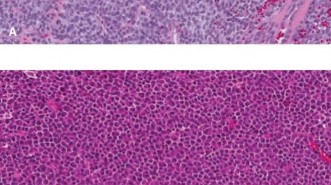

Ewing sarcoma (ES) is a highly aggressive, malignant small round blue cell tumor of bone and soft tissue, belonging to the Ewing sarcoma family of tumors (ESFT). It is characterized by specific chromosomal translocations, most commonly t(11;22)(q24;q12), resulting in the EWS-FLI1 fusion gene, which serves as a molecular hallmark and drives its oncogenesis.

- Histopathological examination, including immunohistochemistry (CD99, NKX2.2) and molecular genetics (EWS-FLI1 fusion), confirms diagnosis and assesses tumor response to neoadjuvant chemotherapy (tumor necrosis percentage), which is a key prognostic indicator.